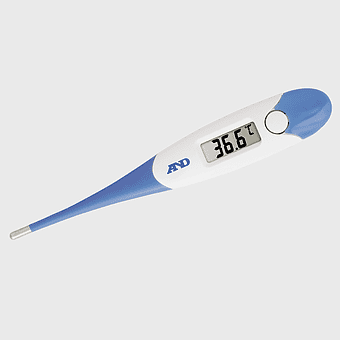

thermometer icon, liquid crystal thermometer, temperature measurement, celsius scale, digital temperature gauge, weather monitoring tools, health monitoring devices -

digital thermometer 37.0, medical device temperature measurement, celsius temperature reading, health care tool, electronic medical instrument, body temperature monitor, digital health equipment -

digital thermometer Celsius, temperature measurement tool, human body temperature gauge, celsius temperature scale, medical temperature reading, clinical thermometer design, health monitoring device -

digital thermometer price, infrared thermometers for sale, medical thermometer measurement, flexible tip thermometer, temperature monitoring device, healthcare temperature tools, electronic temperature gauge -